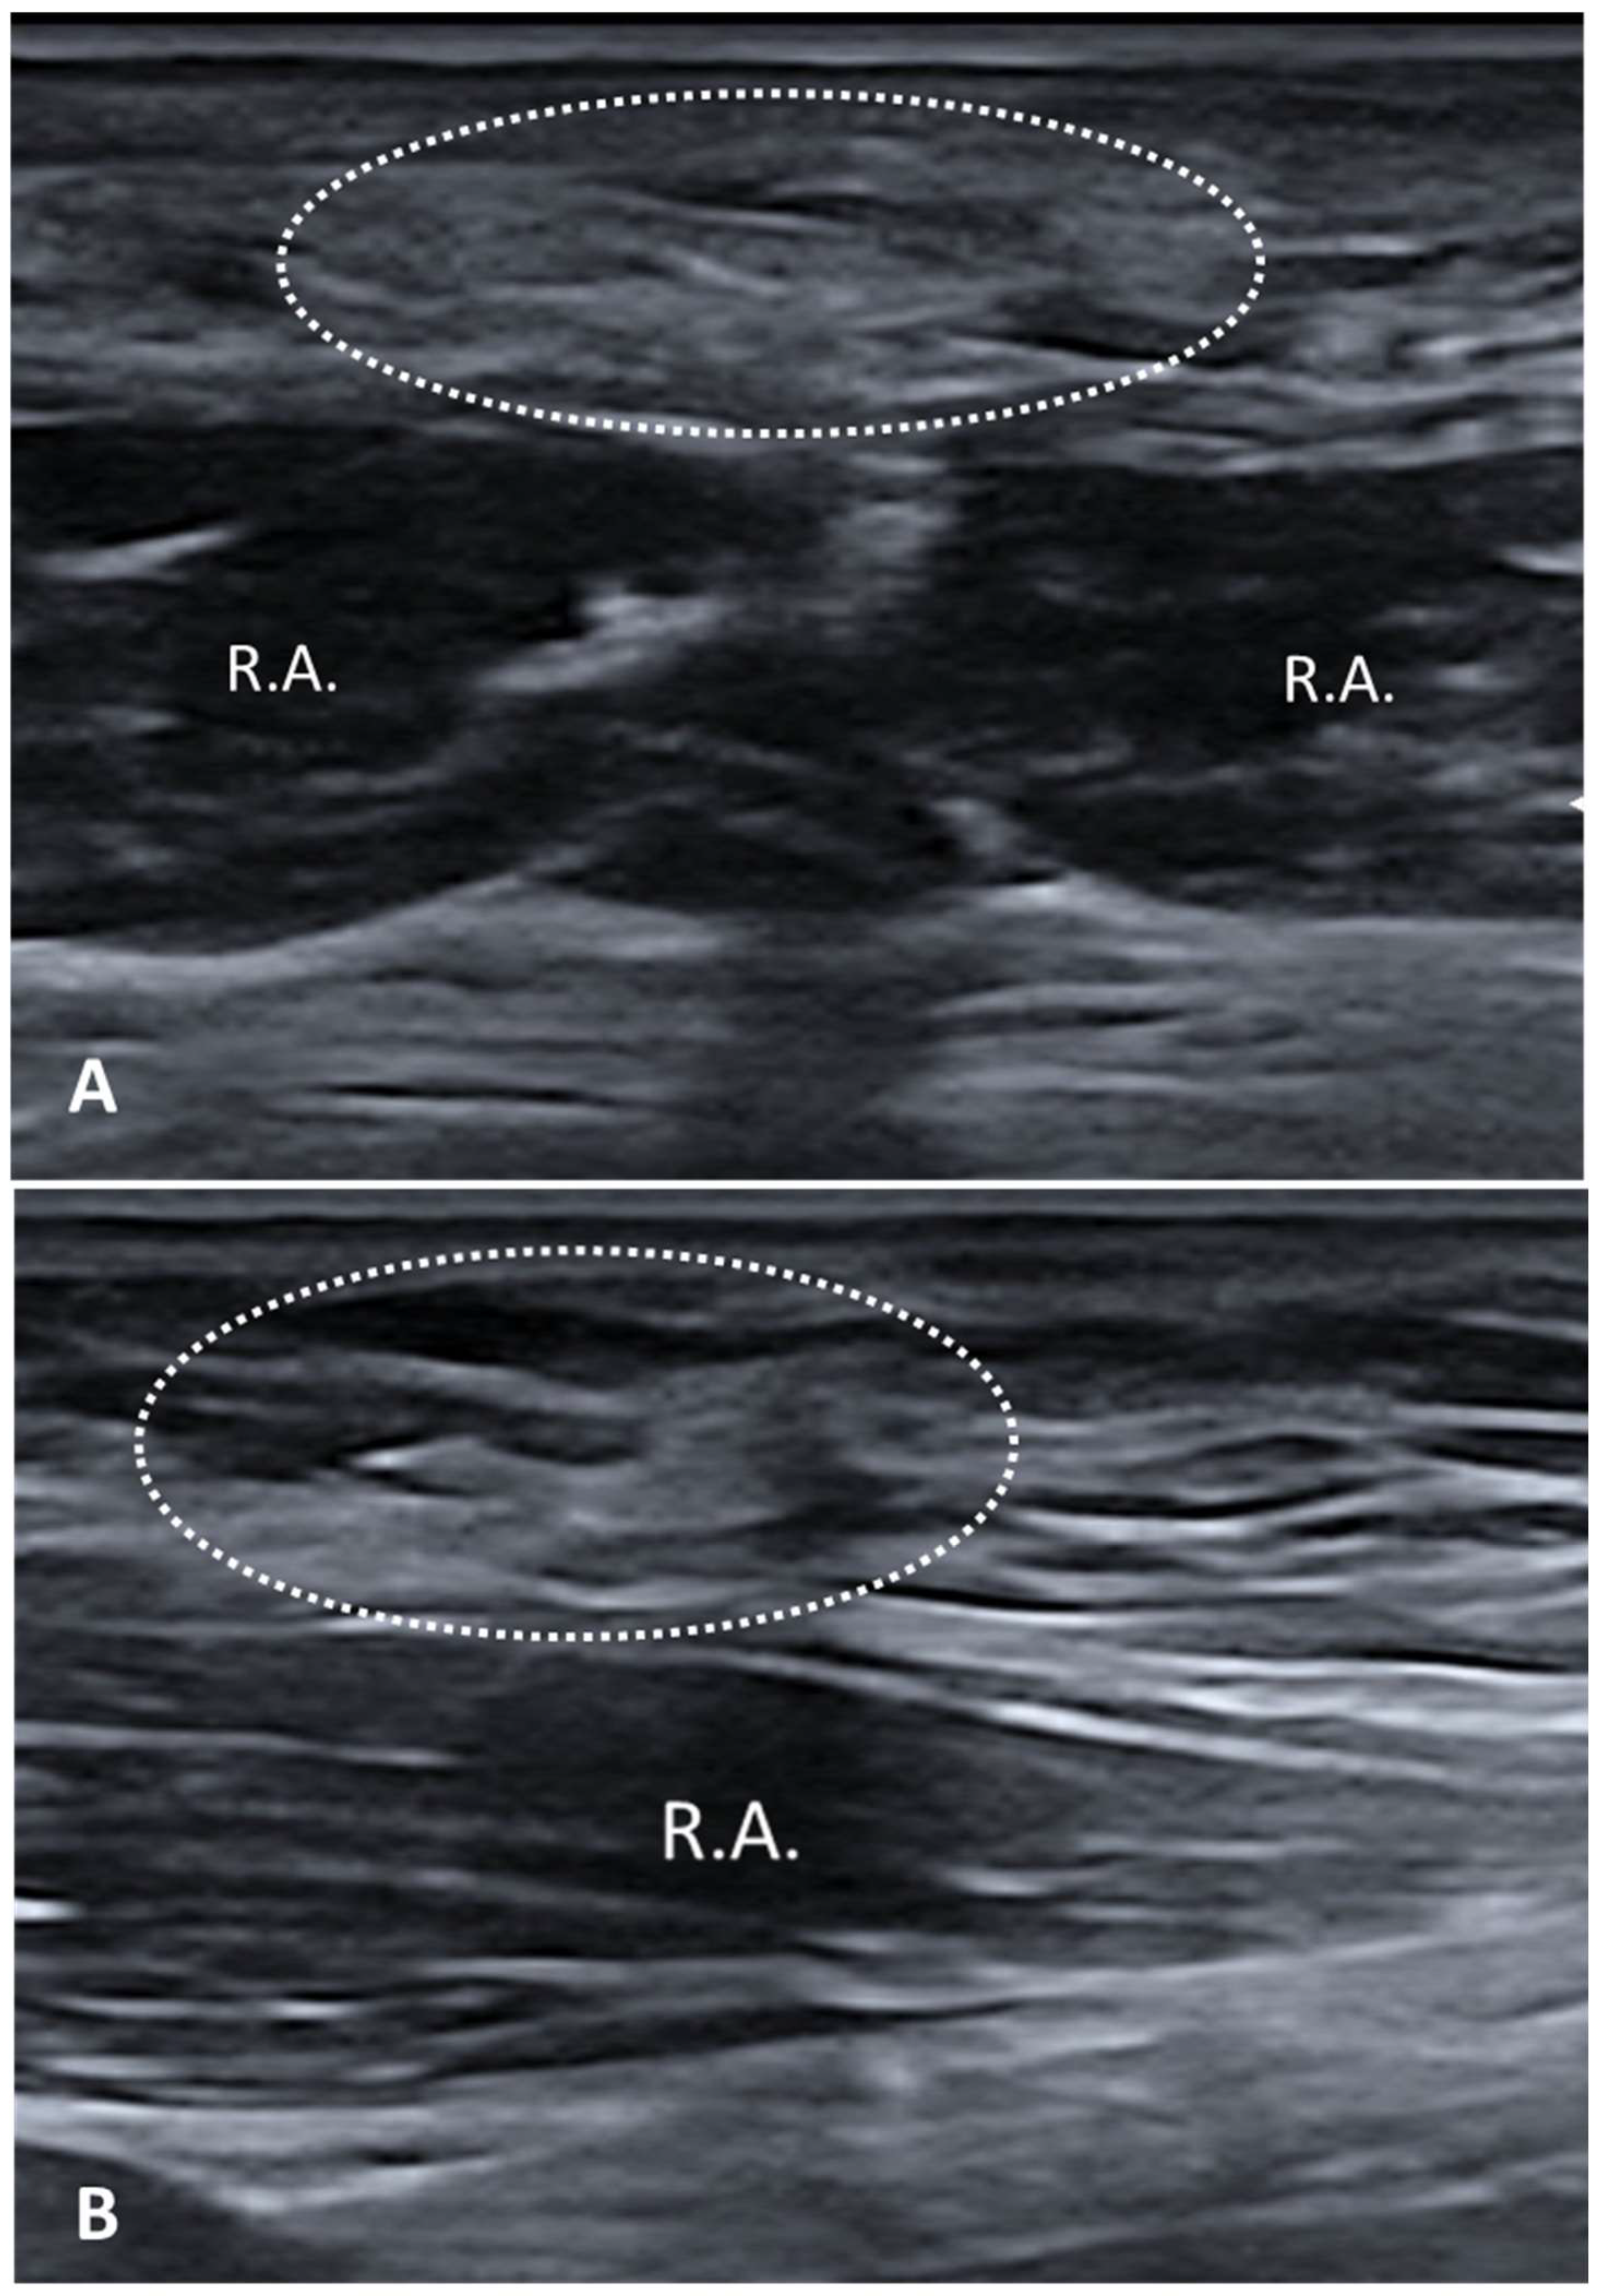

3.5.3. Myofascial Trigger Points